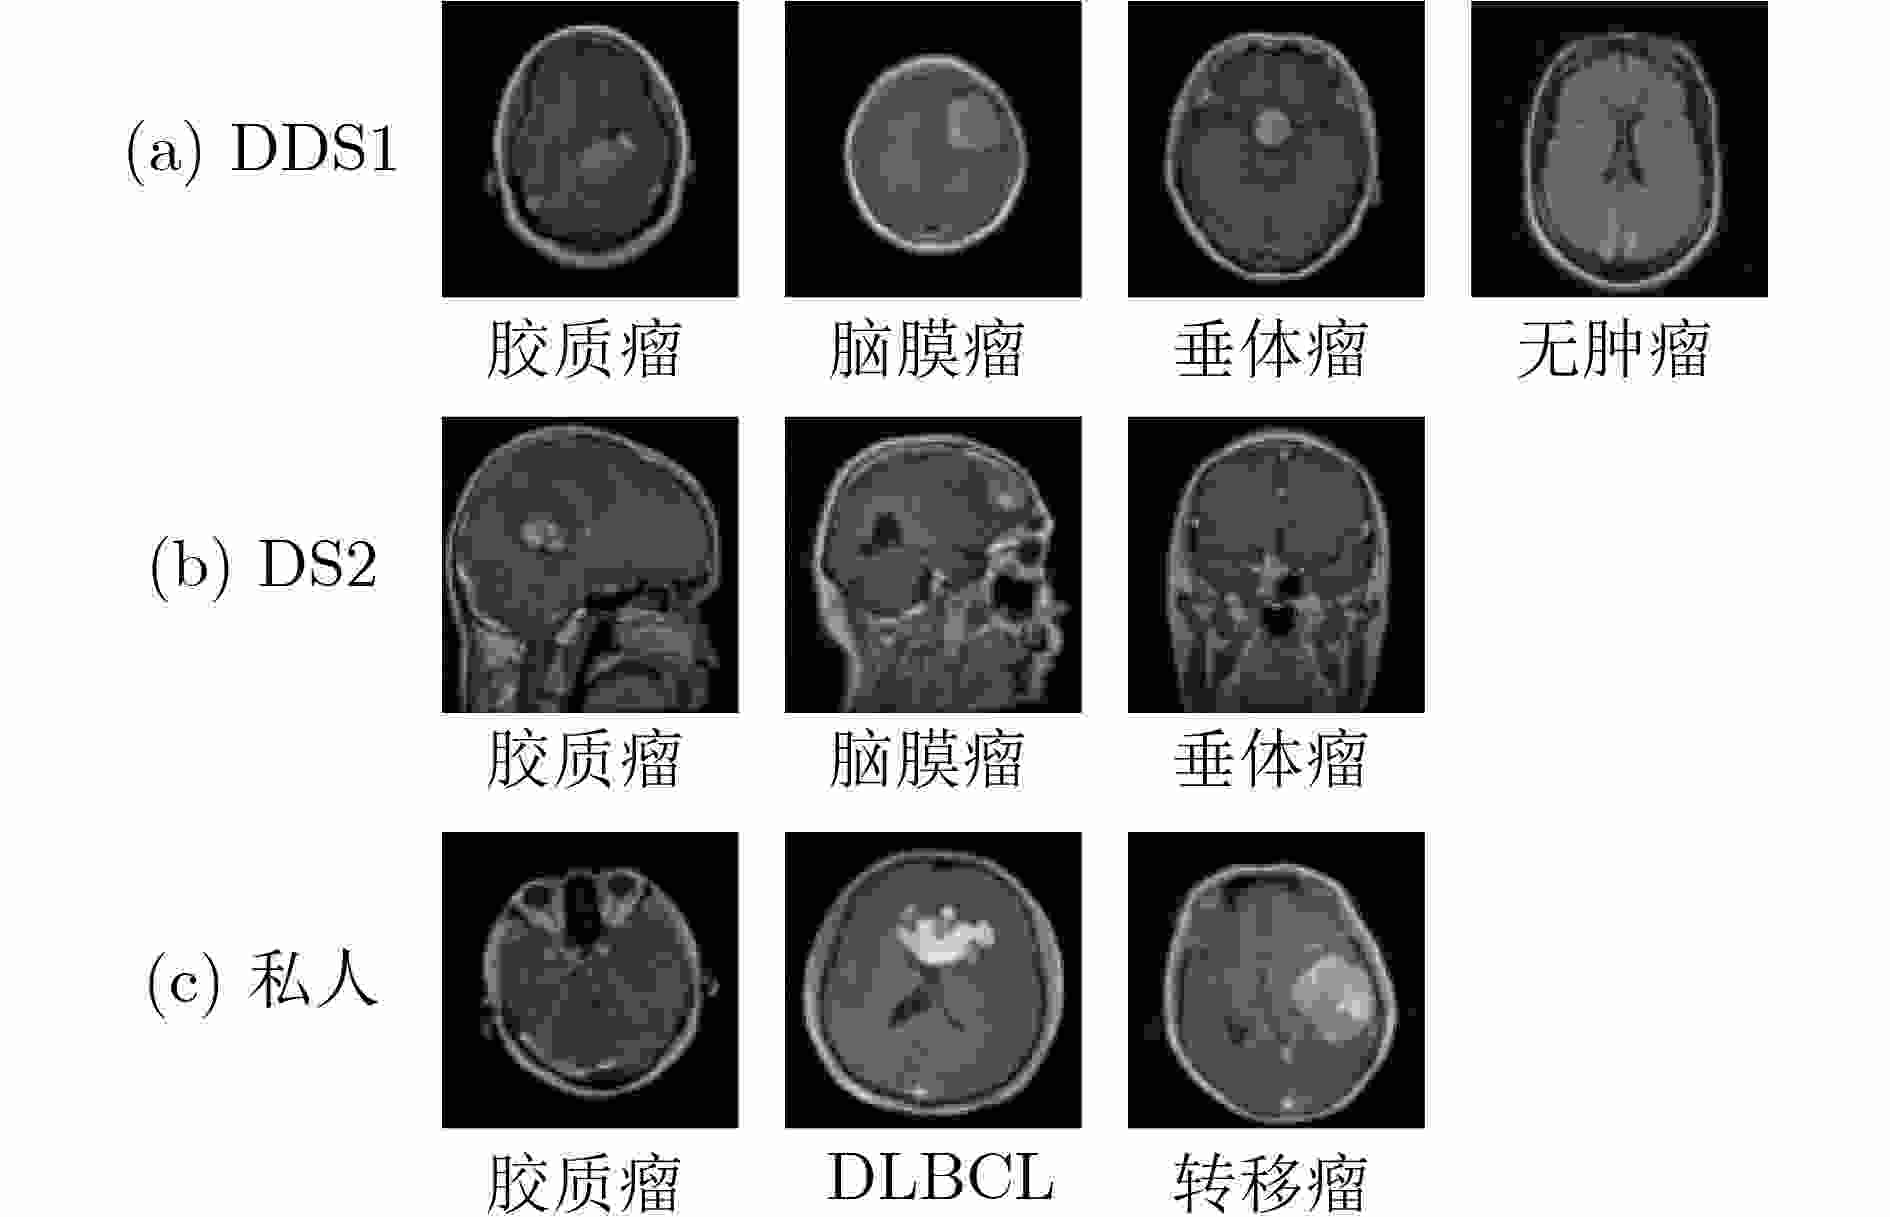

因果推理引导的KAN注意力脑肿瘤分类框架

樊亚文, 王翔, 岳震, 俞晓帆

当前状态:  doi: 10.11999/JEIT250865

[摘要](15) [HTML全文](3) [PDF 3050KB](2)

摘要:

脑肿瘤分类是医学影像分析中的关键任务,但现有深度学习方法在应对扫描参数差异、解剖位置偏移等因素时仍面临特征混淆问题,且难以建模肿瘤异质性引发的复杂非线性关系。针对这一挑战,本文提出一种因果推理引导的KAN注意力分类框架。首先,基于CLIP模型进行无监督特征提取,捕捉MRI数据中的高层语义特征;其次,基于K-means聚类设计混淆均衡度指标,筛选混淆因子图像。并设计因果干预机制,显式引入混淆样本,同时提出因果增强的损失函数以优化模型的判别能力;最后,在预训练ResNet主干网中引入KAN注意力模块,强化模型对肿瘤局部坏死区与强化边缘的非线性关联建模能力。实验表明,所提出的方法在脑肿瘤分类任务中优于传统CNN与Transformer模型,验证了其在判别能力和鲁棒性方面的优势。本研究为医学影像的因果推理与高阶非线性建模提供了新的技术路径。